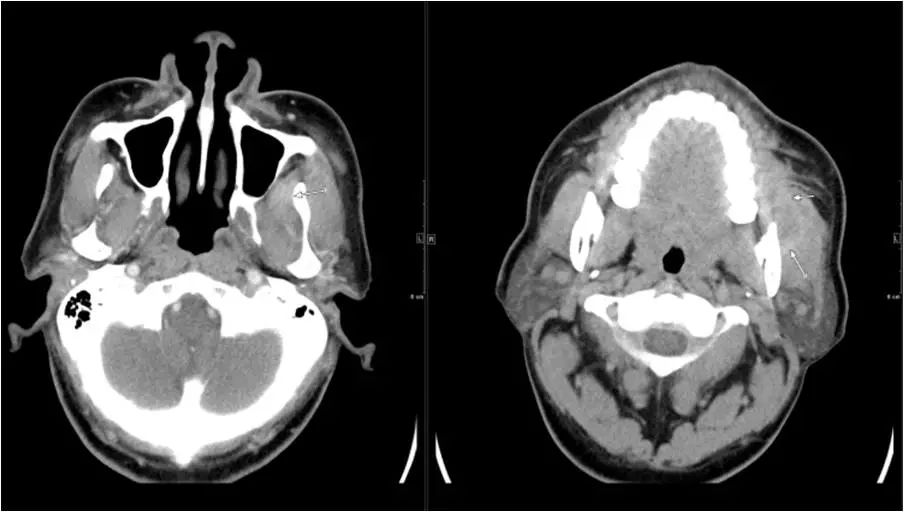

15 多间隙受累

(1)左下后牙疼痛11天余,颈部肿胀10天。

(2)右侧颌面部弥漫性肿胀1月余。